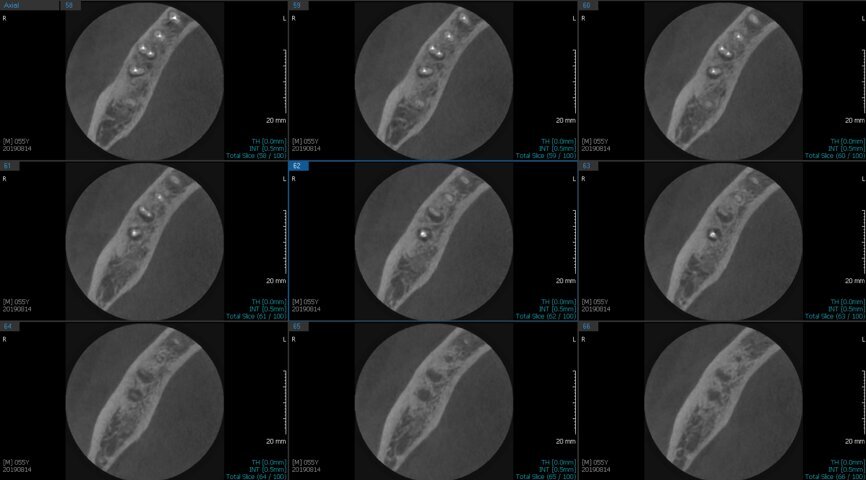

Fig.2a: Pre-op CBCT images of tooth #46: No obturation material in the distal and mesiobuccal canal (a); scanty obturation of the canals and breach of the floor of the pulp chamber, no obturation beyond a few millimetres down the orifice (b & c); radiolucency in the furcation area and periapical region of both roots (d -g).

Fig.2b: Pre-op CBCT images of tooth #46: No obturation material in the distal and mesiobuccal canal (a); scanty obturation of the canals and breach of the floor of the pulp chamber, no obturation beyond a few millimetres down the orifice (b & c); radiolucency in the furcation area and periapical region of both roots (d -g).

Fig.2c: Pre-op CBCT images of tooth #46: No obturation material in the distal and mesiobuccal canal (a); scanty obturation of the canals and breach of the floor of the pulp chamber, no obturation beyond a few millimetres down the orifice (b & c); radiolucency in the furcation area and periapical region of both roots (d -g).

Fig.2d: Pre-op CBCT images of tooth #46: No obturation material in the distal and mesiobuccal canal (a); scanty obturation of the canals and breach of the floor of the pulp chamber, no obturation beyond a few millimetres down the orifice (b & c); radiolucency in the furcation area and periapical region of both roots (d -g).

Fig.2e: Pre-op CBCT images of tooth #46: No obturation material in the distal and mesiobuccal canal (a); scanty obturation of the canals and breach of the floor of the pulp chamber, no obturation beyond a few millimetres down the orifice (b & c); radiolucency in the furcation area and periapical region of both roots (d -g).

Fig.2f: Pre-op CBCT images of tooth #46: No obturation material in the distal and mesiobuccal canal (a); scanty obturation of the canals and breach of the floor of the pulp chamber, no obturation beyond a few millimetres down the orifice (b & c); radiolucency in the furcation area and periapical region of both roots (d -g).

Fig.2g: Pre-op CBCT images of tooth #46: No obturation material in the distal and mesiobuccal canal (a); scanty obturation of the canals and breach of the floor of the pulp chamber, no obturation beyond a few millimetres down the orifice (b & c); radiolucency in the furcation area and periapical region of both roots (d -g).

When I had a close look at the preoperative radiograph from the referring dentist (Fig. 1a), I observed that there was insufficient obturation of the mesial canals and almost no obturation of the distal canal. Both roots displayed periapical radiolucency. The clinical examination revealed a Grade I mobility, and the tooth was tender to percussion. The periodontal examination ruled out any pockets and loss of attachment. We took an intra-oral periapical radiograph (Fig. 1b), from which we observed the loss of coronal structure and a large radiolucent area over the furcation area and the periapical area of both the mesial and the distal roots. A CBCT scan of tooth #46 was advised to check for any details that may have been missed in the intra-oral periapical radiograph (Figs. 2a–g). From the CBCT scan, it could be observed that there was inadequate obturation of the distal canal on the horizontal plane, no obturation beyond the middle third in the mesial canals and a breach of the floor of the pulp chamber. The questionable prognosis was explainedto the patient, and written consent was obtained.